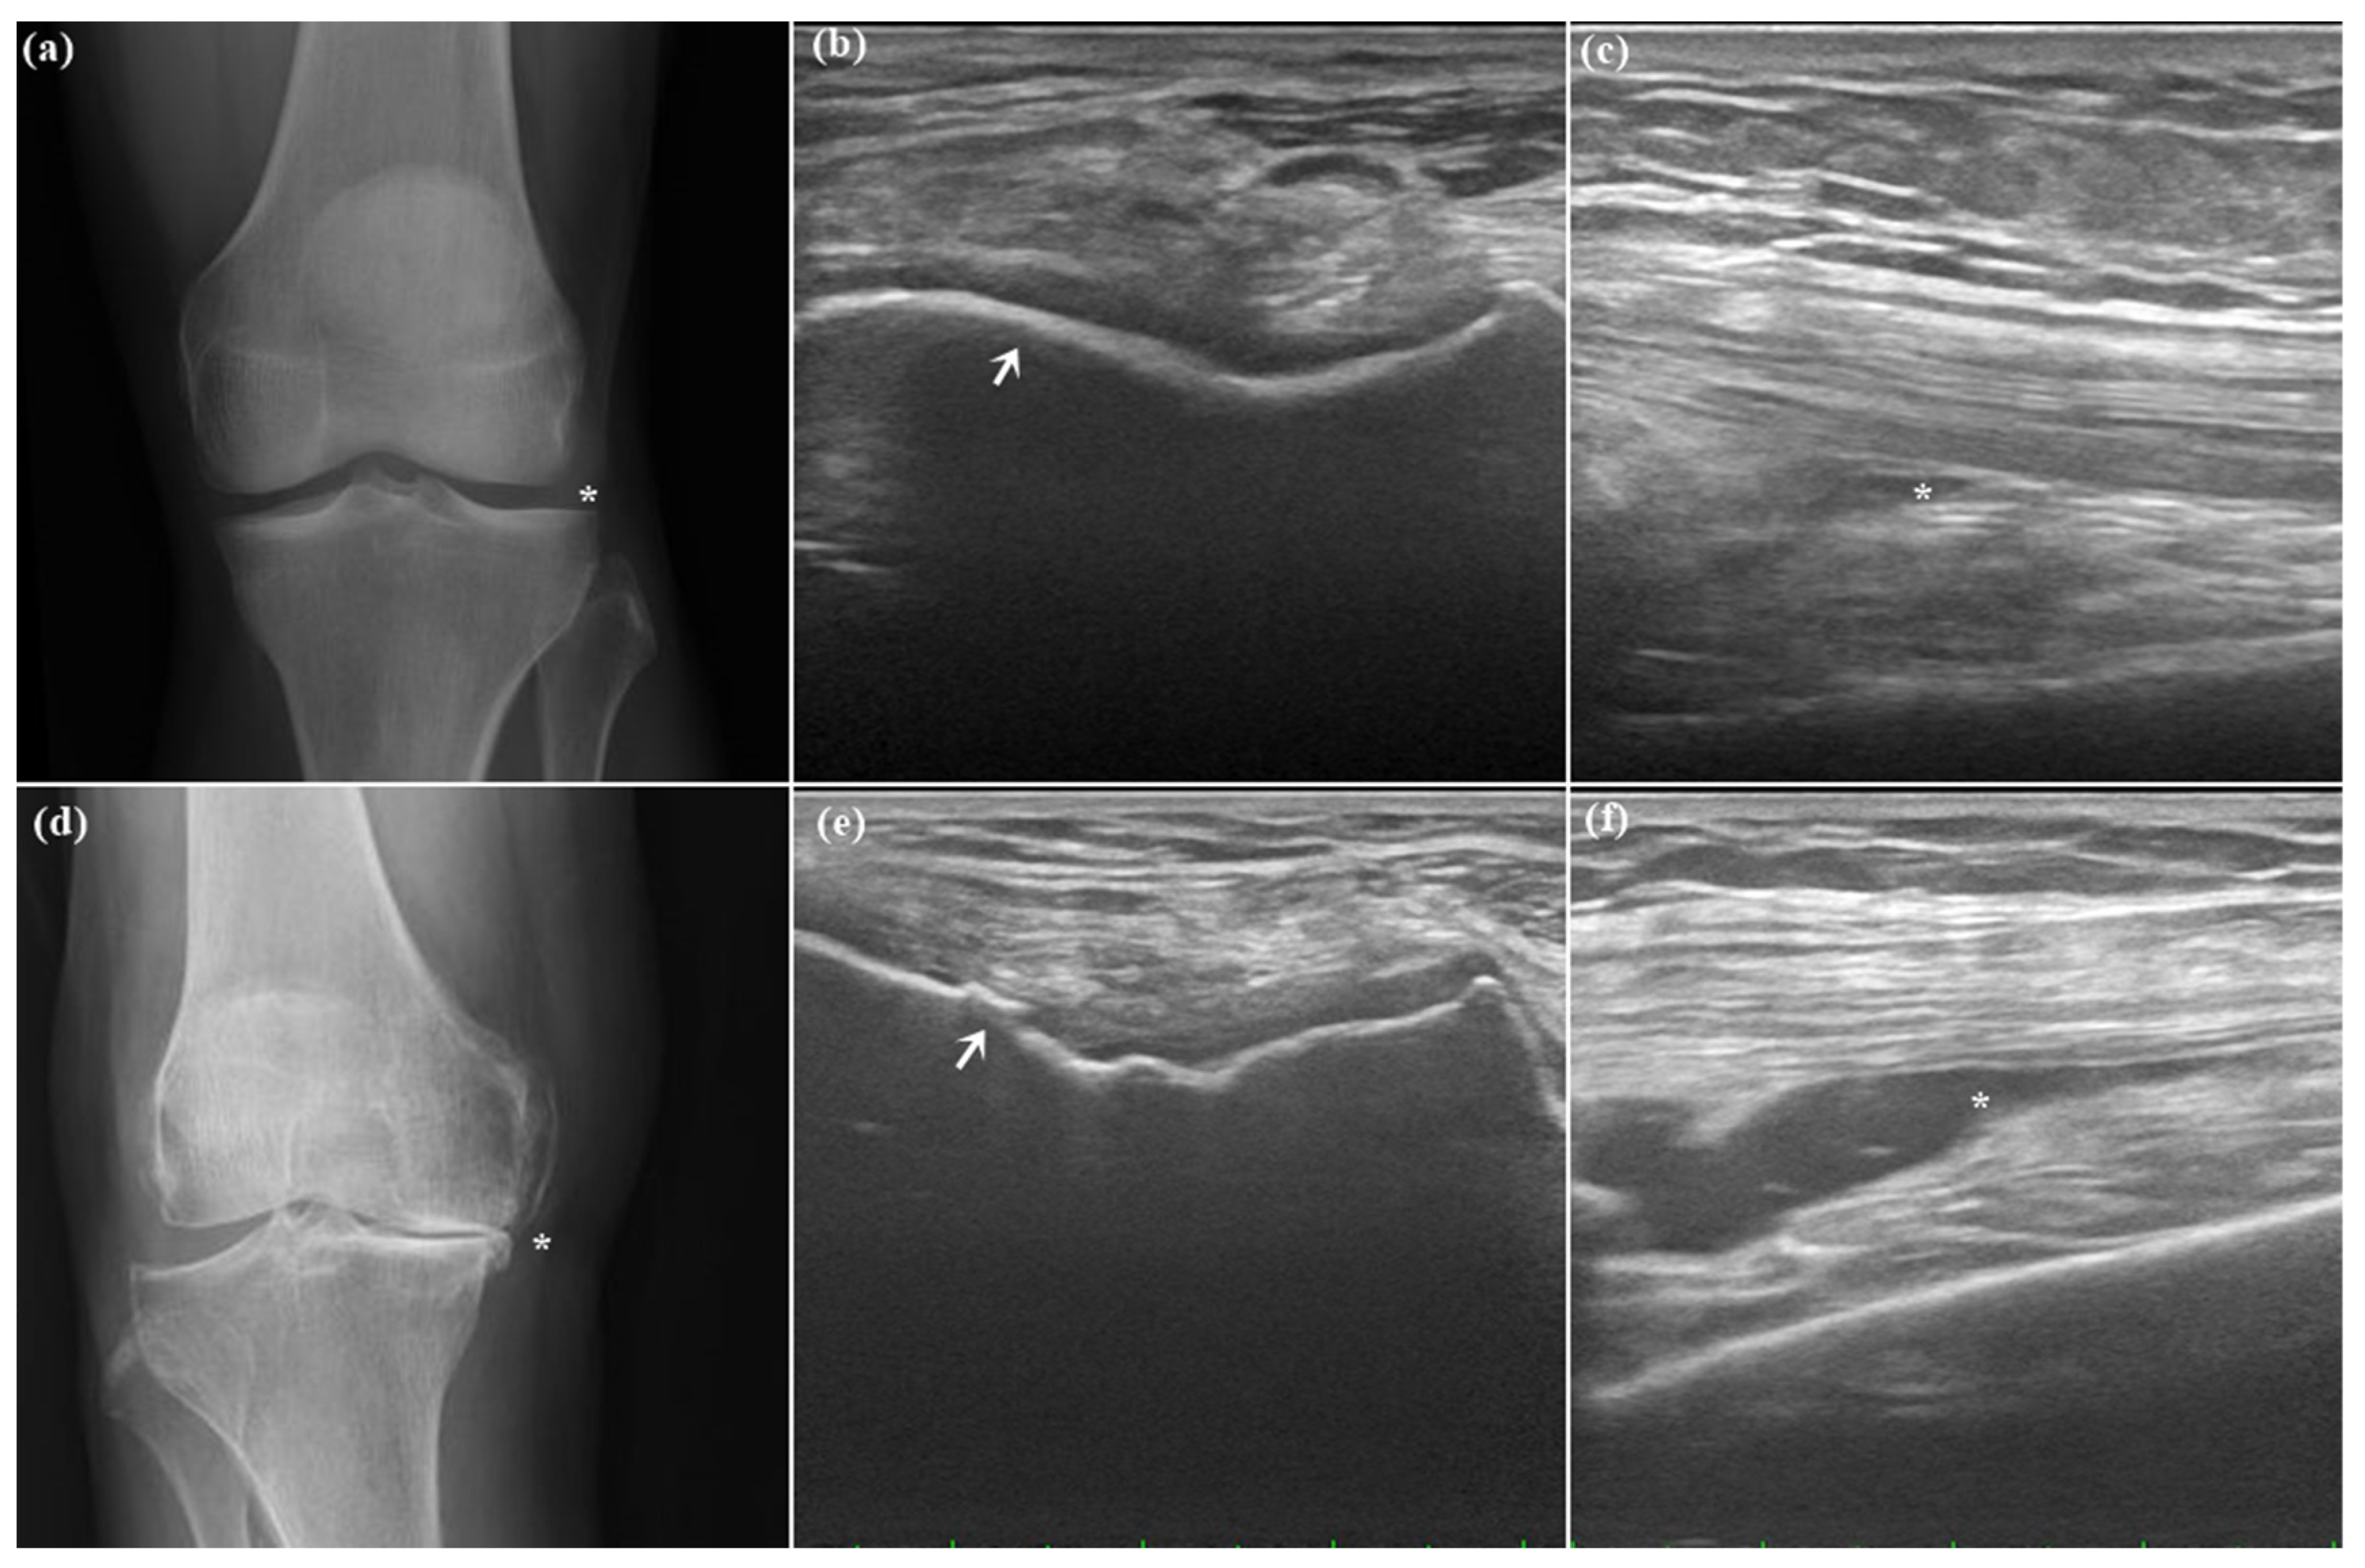

2.2. Ultrasound Synovial Outcome

4.3. Ultrasound Evaluation